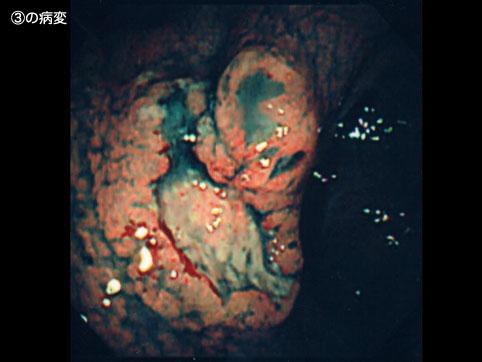

Tumor Linfático Maligno tipo células T del Estómago que evidenció mejoría debido a la radioterápia

Tumor Maligno del Sistema Linfático/Linfoma Maligno

estómago(región)/fornix

Endoscopia

diámetro mayor del tumor

40 -

múltiples tumores(en un mismo órgano)

presente(simultáneo)

múltiples tumores(en varios órganos)